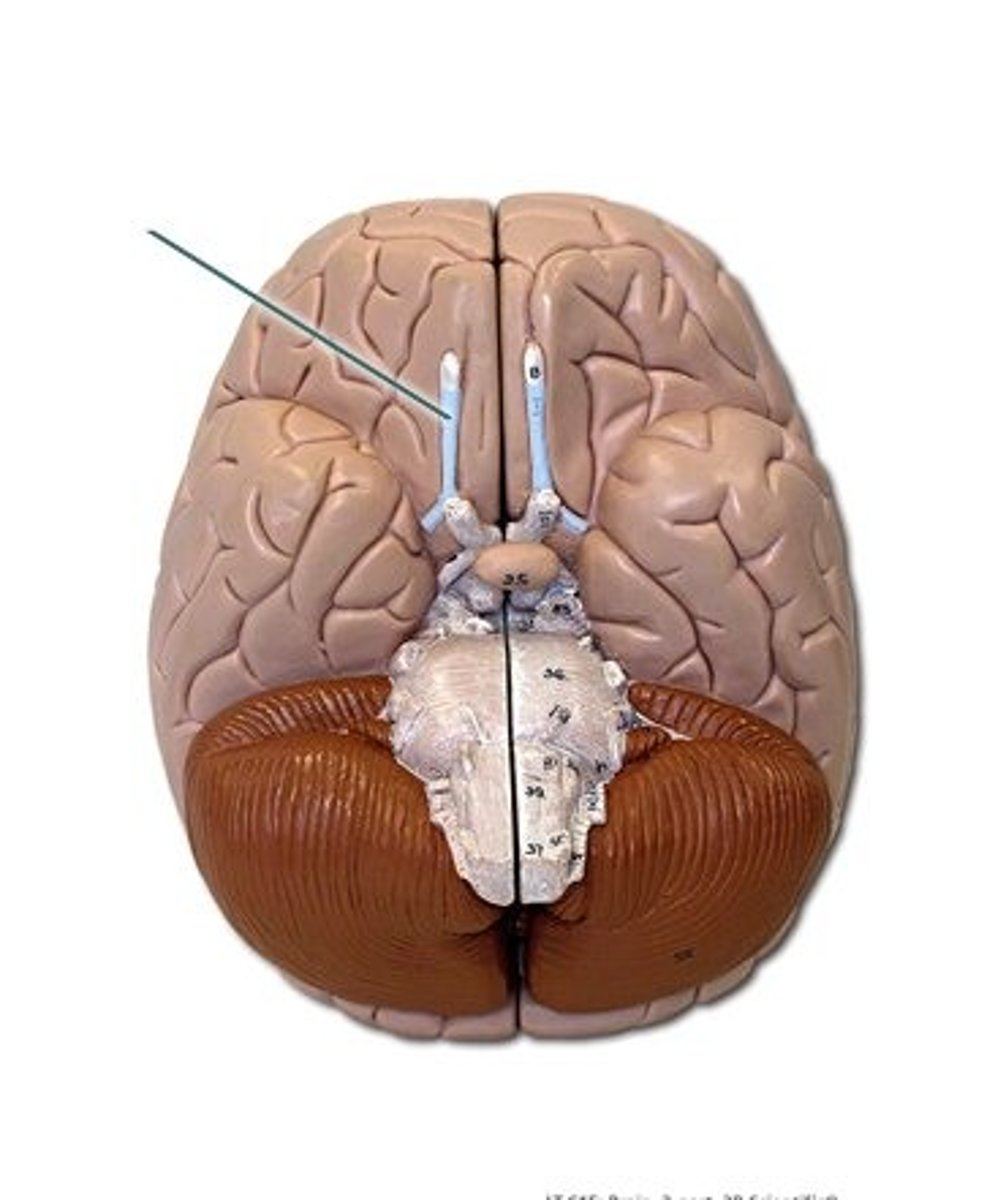

optic chiasm

point at which optic nerve fibers cross in the brain

optic tracts

the continuation of the optic nerve fibers beyond the optic chiasma

longitudinal fissure

deep cleft that separates cerebral hemispheres

corpus callosum

A thick band of axons that connects the two cerebral hemispheres and acts as a communication link between them.